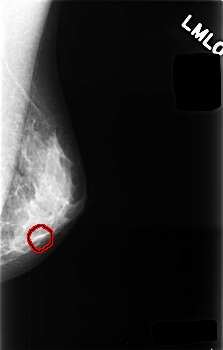

C_0477_1.LEFT_MLO

LEFT_MLO LINES 4544 PIXELS_PER_LINE 2896 BITS_PER_PIXEL 12 RESOLUTION 50 OVERLAY

FILE: C_0477_1.LEFT_MLO.OVERLAY

TOTAL_ABNORMALITIES 1

ABNORMALITY 1

LESION_TYPE CALCIFICATION TYPE PUNCTATE DISTRIBUTION CLUSTERED

ASSESSMENT 4

SUBTLETY 3

PATHOLOGY BENIGN

TOTAL_OUTLINES 1

BOUNDARY